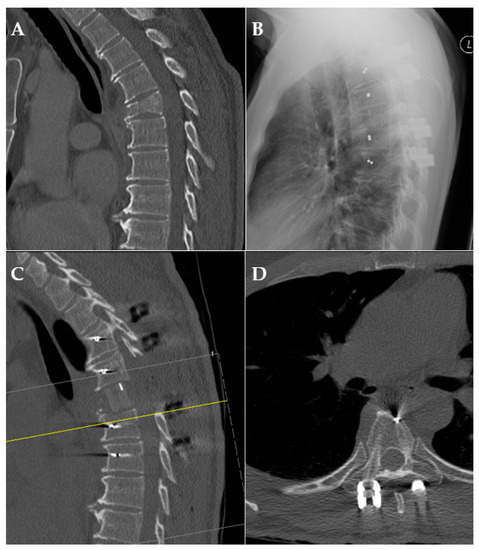

Figure 4.

Exemplary case of pre-/postoperative CT scan and X-ray. (A): preoperative CT scan of a pathological fracture of the thoracic spine; (B): X-ray after posterior fusion; (C,D): CT scan after posterior fusion and anterior reconstruction demonstrating radiolucency.